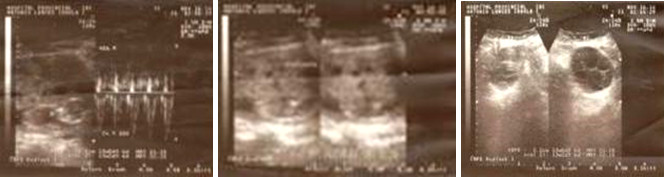

Volver a los detalles del artículo Preeclampsia grave y mola hidatiforme embrionada con feto vivo